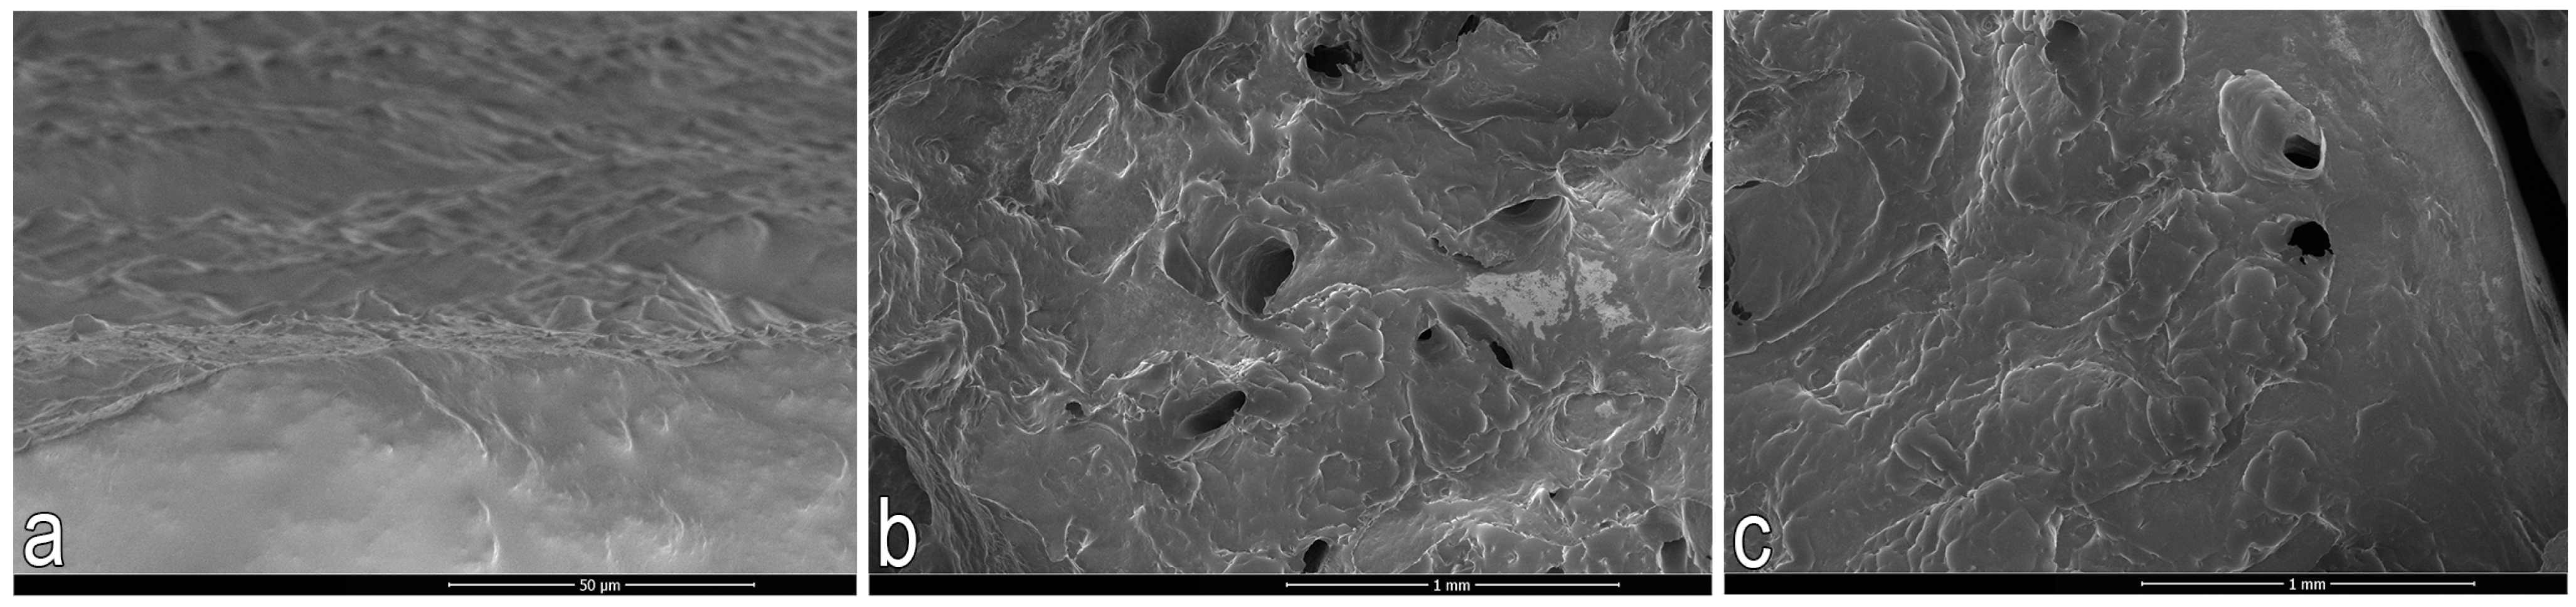

2.3.2. Scanning Electron Microscopy (SEM)